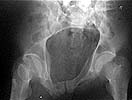

I did as suggested, I performed a 2-stage procedure (posterior sacral osteotomy and anterior take-down of left-sided rami fractures and anterior plate and percutaneous iliosacral screw fixation). It was a difficult and humbling experience. I felt as though the sacral osteotomy was complete and seemed so using intraoperative image views (inlet, outlet and true lateral of the sacrum) however after placing the distractor anteriorly I found that I could not see the sacrum well due to the bulk of the distractor itself. I then replaced it with radiolucent external fixation bars and noted widening of the left anterior SI joint.

Apparently my sacral osteotomy was not complete and the rotational correction (lateral and inferior) was occurring through the SI joint, at least anteriorly. An intraoperative x-ray showed definite improvement of the leg length discrepancy but not complete. I felt that in addition to the rotational correction the left hemipelvis also needed to move inferior as well. Due to the patient's small size, traction on her left leg simply produced pelvic obliquity and I really did not have a way of placing well leg traction which would require a post and at the same time obtain adequate intraoperative image views. Long and the short is I accepted a less than perfect reduction but with leg lengths now with less than 1 cm difference clinically and radiographically and I fused her left SI joint. No post-op nerve deficits. It was definitely a learning experience.

Any and all feed back is appreciated. Postop pics enclosed.

Intraoperative fluoro can be misleading regarding deformity corrections...maybe consider plain films when needed. Notice this lady's external rotation of the left hemipelvis postop and its impact on the acetabular coverage...see the inlet(caudal) view with attention to the ischial spine assymetry.